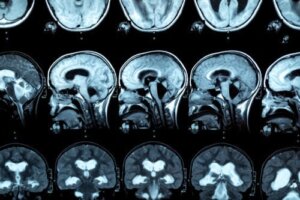

W diagnostyce tej patologii wykonuje się MRI, aby zaobserwować zmiany w ciele modzelowatym. W związku z tym badania wskazują, że osoby z zaburzeniami związanymi z używaniem alkoholu wykazują zmniejszenie przedniej, środkowej i tylnej grubości ciała modzelowatego, a także różnice w wielkości płata czołowego i bruzd korowych.

Zgrubienie ciała modzelowatego można również dostrzec, wykonując badania obrazowe mózgu. W niektórych przypadkach występują objawy zespołu odłączenia międzypółkulowego.